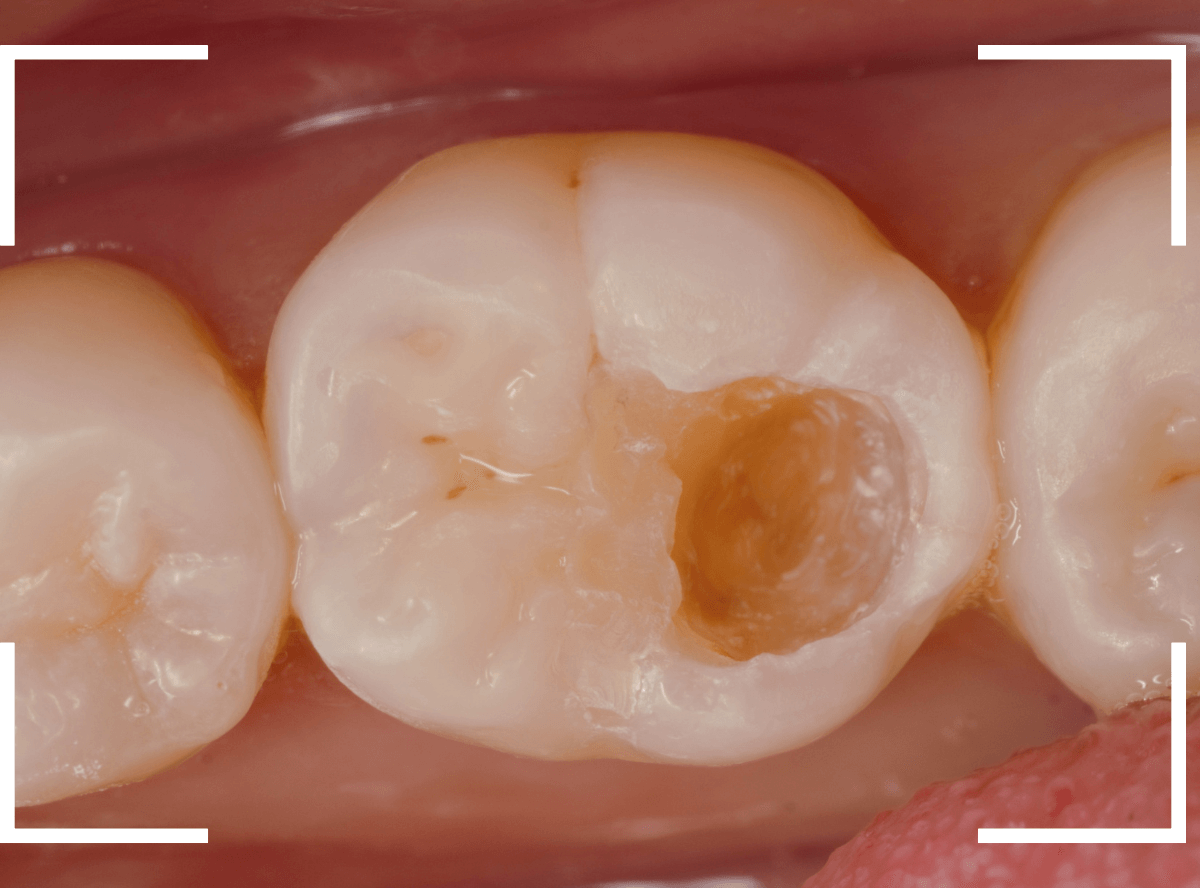

Case.18 虫歯なのは間違いないが、境界がはっきりしない

「つめものが外れて、噛むと痛い」という訴えで来院された患者さんさんです。

一見で、表面が虫歯になっているのと、レジンが劣化しているのがわかります。

レントゲン写真で確認します。

〇部が当該の歯です。

症状もあるので、虫歯が深そうですが、全体がもやっとして、どこからどこまで虫歯なのかはっきりわかりません。

まれに、こんな時もあります。

レジンを外し、虫歯の処置を進めます。

慎重に虫歯を除去し、一安心か、という寸前で(〇部、小さく出血しているところ)露髄してきました。

神経を除去しないとダメかもしれません。。。

神経を保護するお薬をつめて、経過観察します。

痛みが出ませんように。。。